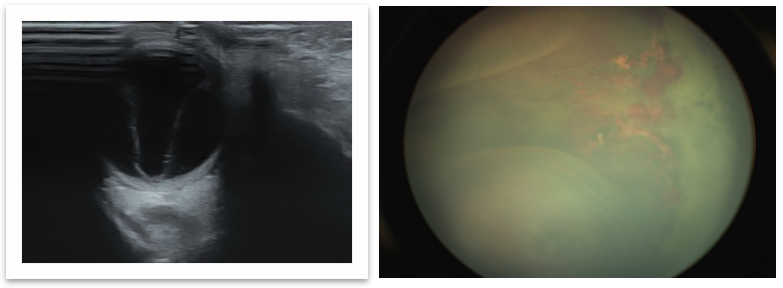

男童,2岁3个月,因体检发现左眼瞳孔呈猫眼状1个月就诊。术前B超检查可见视网膜高度脱离,巩膜外放液术中截屏可见脱离的视网膜贴近晶状体,异常血管清晰可见,背景呈黄色系视网膜下广泛的脂质渗出所致,属于Coats病3B期。本例患儿存在广泛视网膜异常血管并高度脂质性脱离,给予了巩膜外放液联合眼内光凝异常血管手术。联合抗VEGF治疗可以降低异常血管通透性并减轻炎症反应,目前临床上尚无共识,一些小样本临床研究报告首次抗VEGF治疗后6-9个月可发生纤维化甚至牵拉性视网膜脱离,但也有调查显示两者无关。本例患者光凝联合抗VEGF治疗随访2年多,渗出吸收、视网膜复位,无观察到纤维化并发症。

术前B超检查:视网膜全脱离

术中截图:眼表照明下即可看到高度隆起的视网膜及其扩张的异常血管、视网膜下脂质渗出